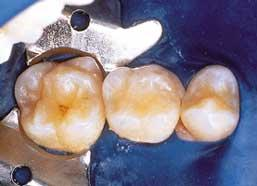

• The use of a rubber dam to isolate 9 (Figure 1) for sterilization purposes, is always recommended. On newly erupting molars in small children and young teenagers, there are times I find the use of a rubber dam just unachievable, but always use one if possible. For best results always maintain a dry surface.

• Clean all surfaces to be sealed by rinsing with an oil-free water spray. Dry or apply a cleaning agent (Figure 2), and then rinse with water spray and dry. Note: Cleaning also may be accomplished with air abrasion.